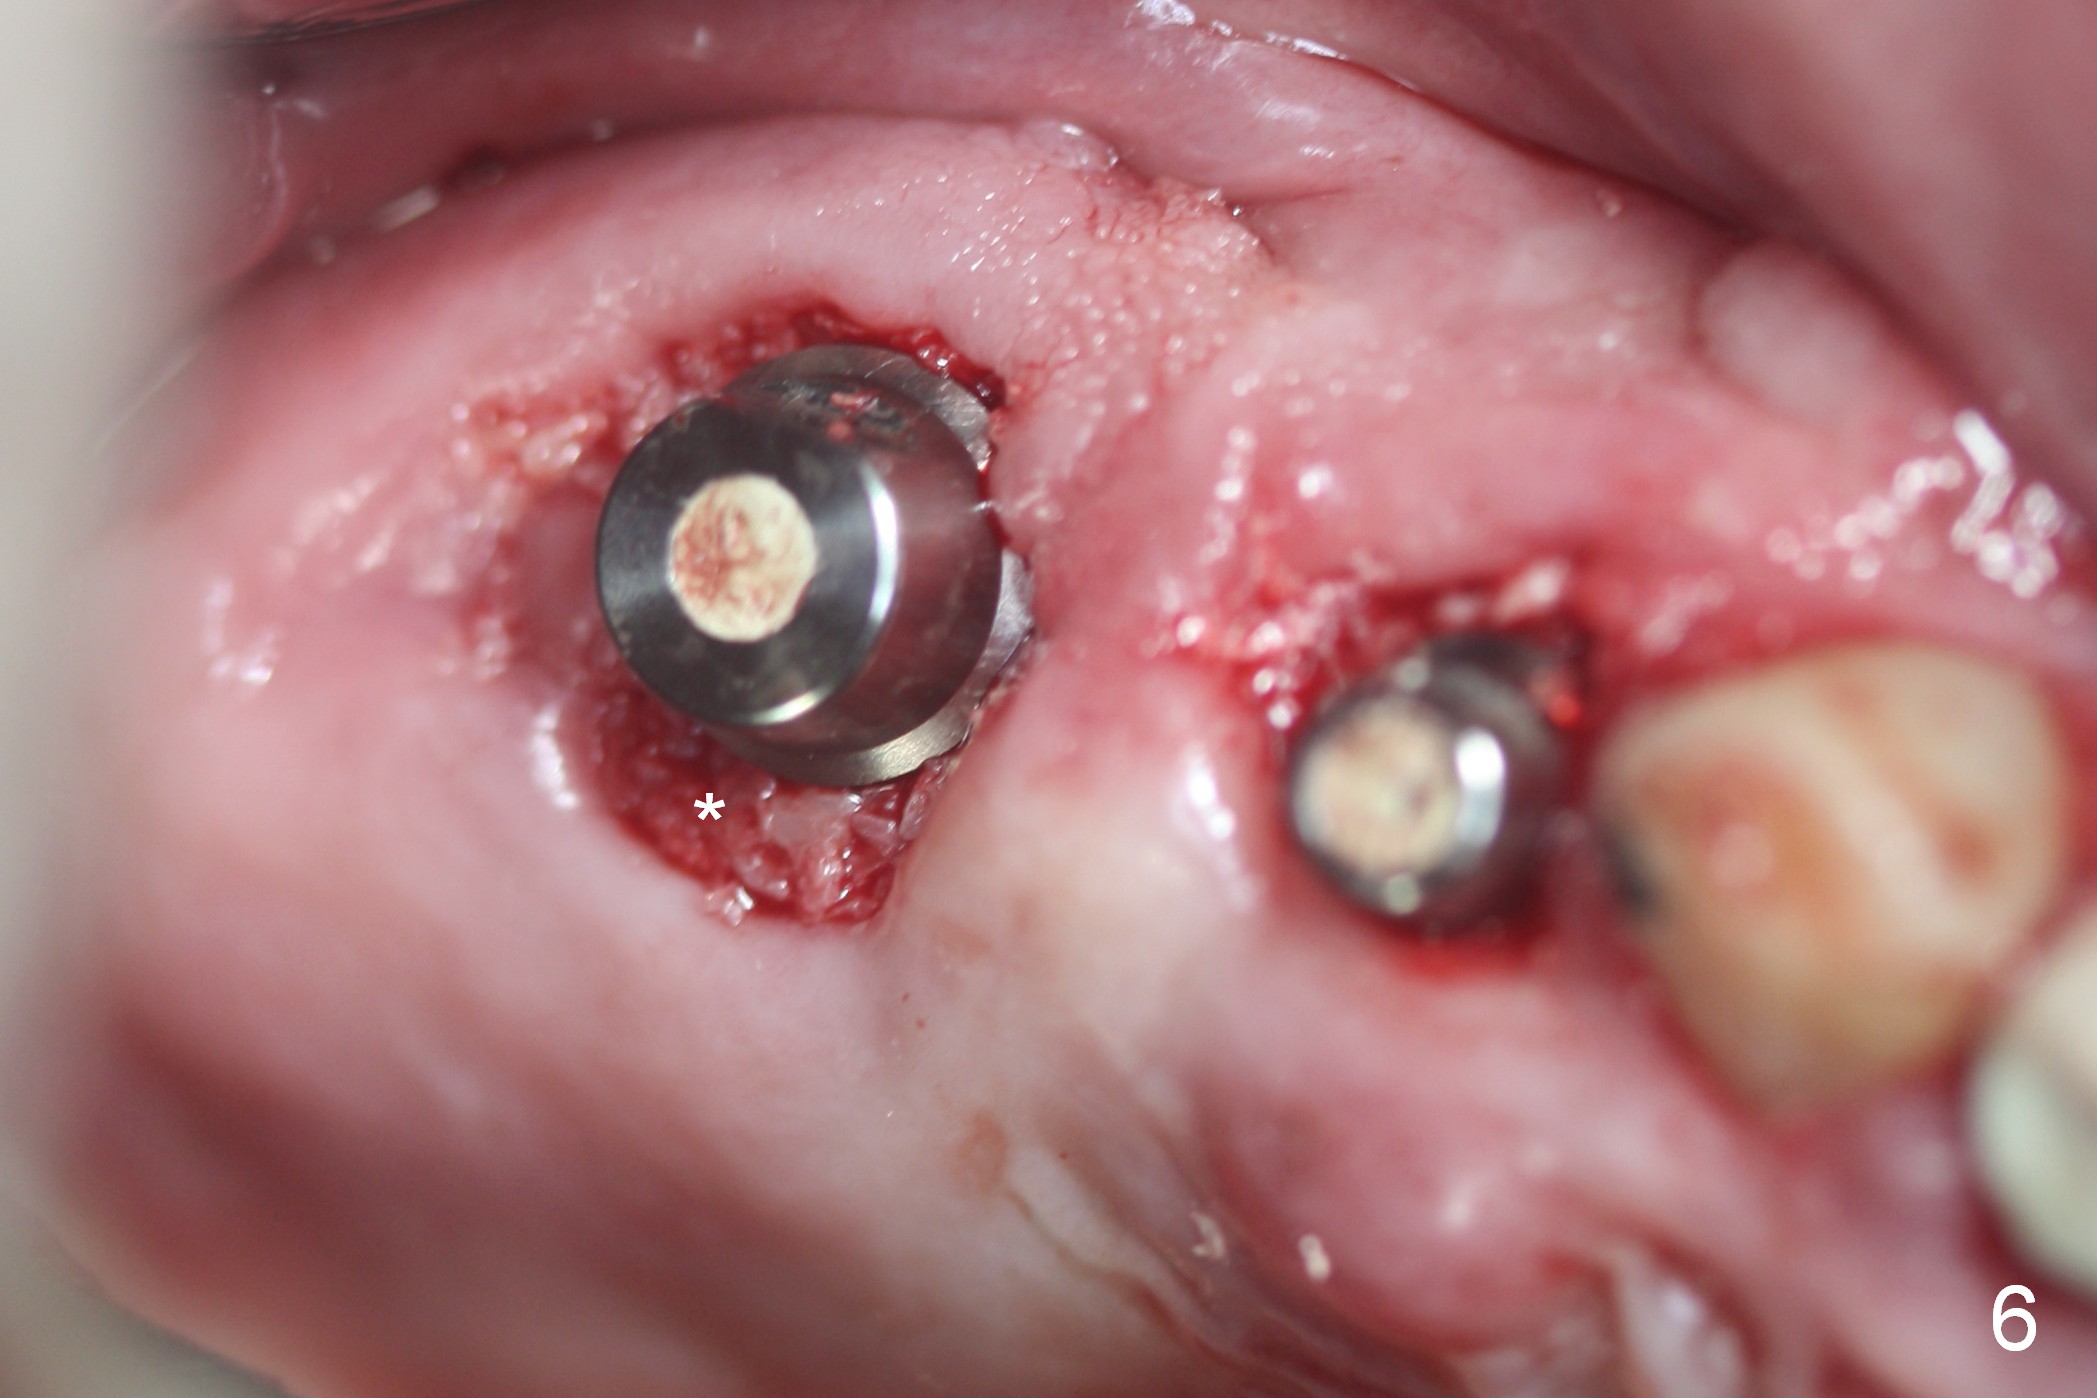

Preop photos show generalized gingival hyperplasia (hypertension med (Amlodipine, Calcium Channel Blocker), Fig.1 *), palatal (Fig.2<) and buccal (Fig.3 B) abscesses originated from the tooth #5. There is a smaller abscess buccal to the tooth #3 (not shown). After extraction, the buccal and palatal plates of the teeth #3 and 5 are found basically non-existent. When taps are placed, large socket defects are evident (Fig.4 *). In addition to sinus lift at #3 (Fig.5 black *), mineralized cancellous and cortical allograft (.5-1 and 1-2 mm) is placed around the implants with healing screws in place (white *). After the healing screws are removed and cemented abutments are placed, more allograft is packed (Fig.6-8 *). Closing the "dead" space in step may prevent immediately postop infection and peri-implantitis.

There is no infection around the implants 1 months postop (Fig.9,10). In fact infection mesial to #6 is more severe than preop (Fig.9 arrowhead, Fig.11). When the provisionals are removed for trimming, there is yellowish bone graft around the abutments, which is apparently not incorporated by the body (Fig.9,10 *). It is easily removed by spraying water. The margin of the abutment at #5 is subgingival; an abutment with a longer cuff should be changed next visit.